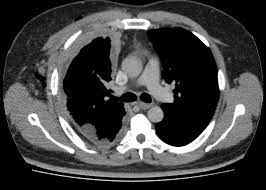

Inhibidores de puntos de control inmunológico antes de la nefrectomía para el carcinoma de células renales

Este artículo revisa la evidencia actual y los ensayos en curso sobre la terapia con inhibidores de puntos de control inmunológico (ICI) neoadyuvante o prenefrectomía en pacientes con carcinoma de células renales (CCR) localmente avanzado y metastásico. Los hallazgos sugieren que la terapia combinada basada en ICI es el estándar de atención como tratamiento de primera línea para pacientes con CCR metastásico; sin embargo, el papel de los ICI neoadyuvantes en el CCR localmente avanzado es un área activa de investigación. JAMA Oncology, 14 de diciembre de 2023.